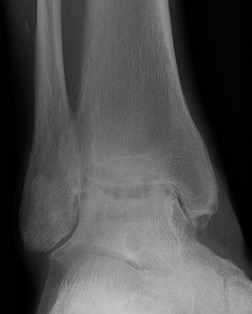

Xray

Ranges from anterior spurring to severe OA

80% of post-traumatic OA is varus

Takakura classification

| 1 | Early sclerosis and formation of osteophytes |

| 2 | Narrowing of the medial joint space |

| 3A | Obliteration of the medial joint space with subcondral bone contact |

| 3B | Obliteration of joint space over roof of talar dome, with subchondral bone contact |

| 4 | Obliteration of joint space with complete tibiotalar contact |

Type 1: Anterior spurs

Type 3A: Obliteration of medial joint space Type 3B: Obliteration medial joint space plus tibio-talar contact with varus

Type 4 complete obliteration